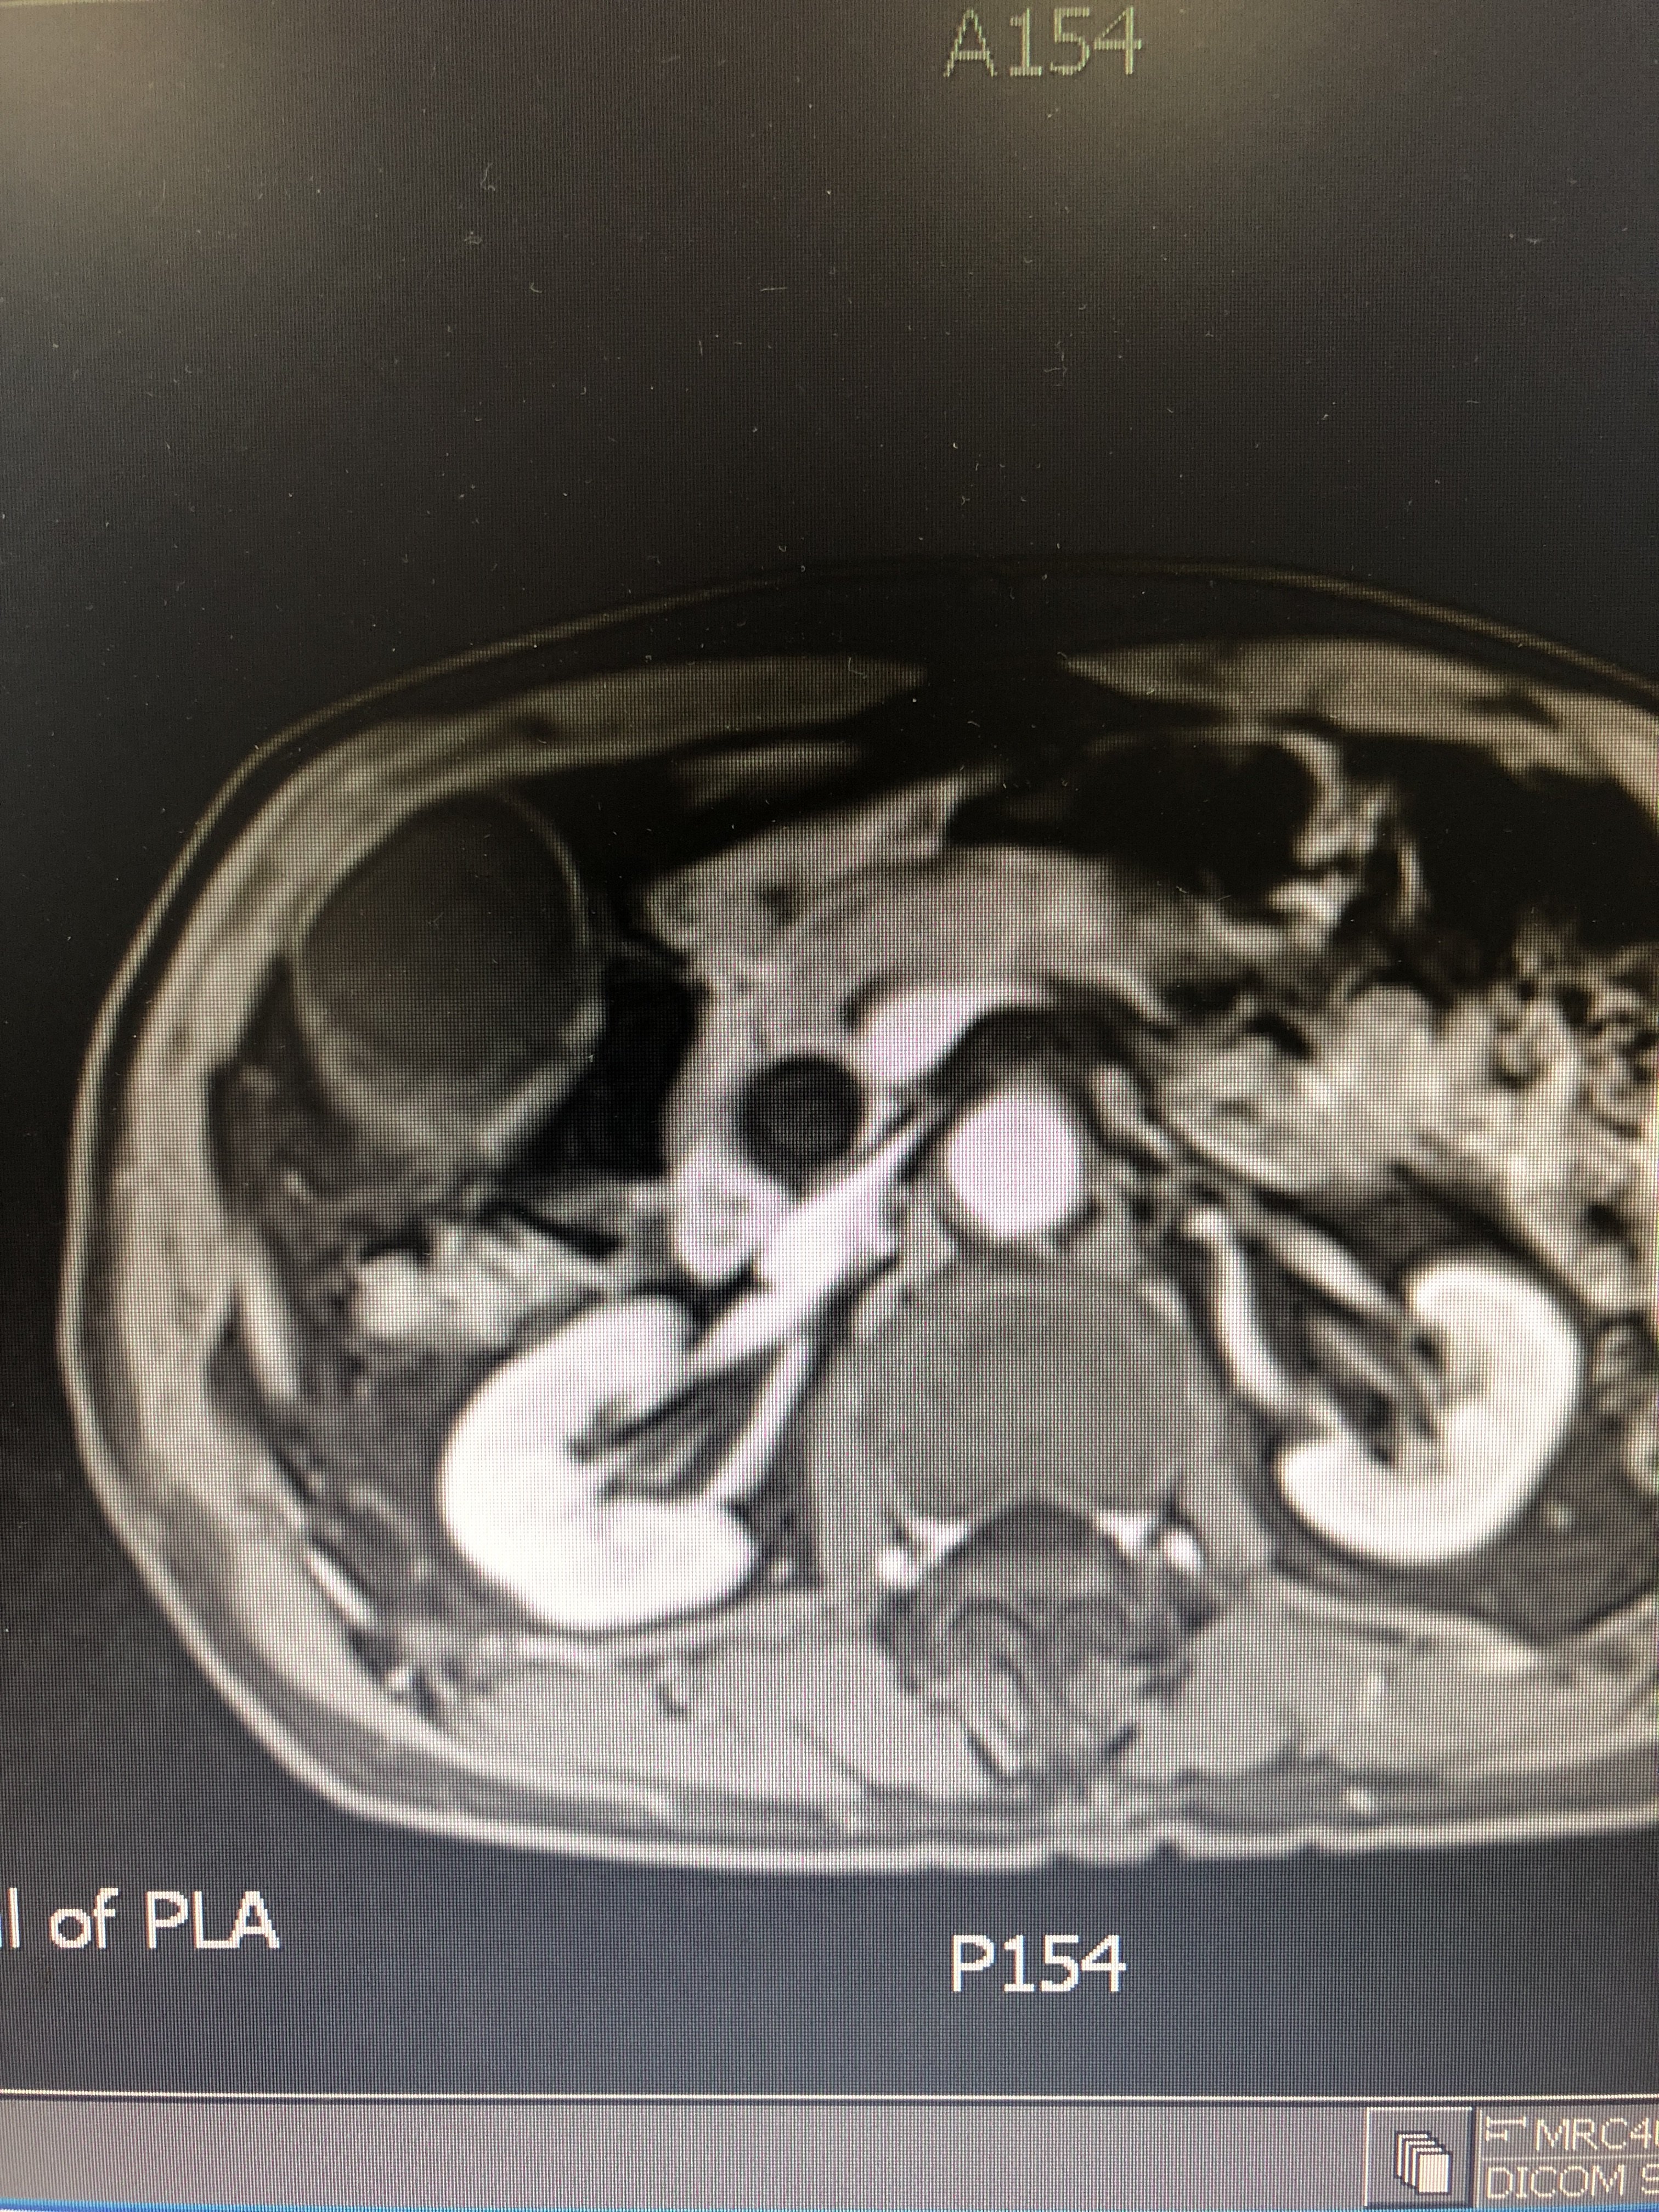

胆管下端狭窄即缩窄性乳头炎伴胆管扩张并

3024x4032 - 2693KB - JPEG